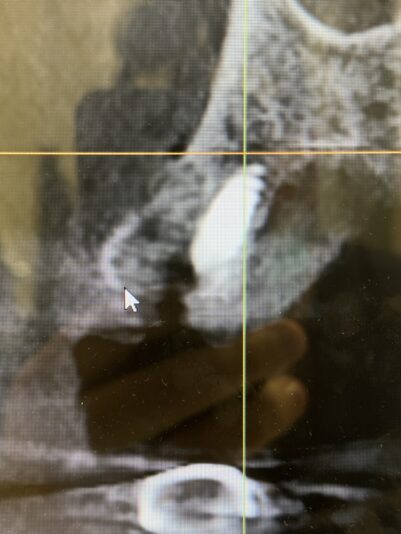

• Here is an update from the previous post…

This shows how we dealt with the complication of a buccal perforation. Luckily, the patient had sufficient width so we removed the implant and placed another implant lingual to that site with better buccal lingual agulation. We then bone grafted the site and perforation and secured a resorbable collagen…

Read more